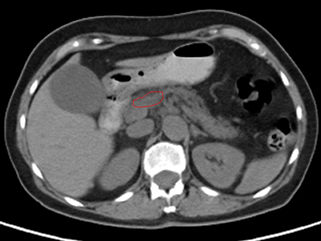

郭林治疗前CT显示肿块,活检证明为胰腺癌

半年后复查CT显示胰腺肿瘤缩小,PET上无活性,提示肿瘤坏死。肝转移灶消失(此图未显示)